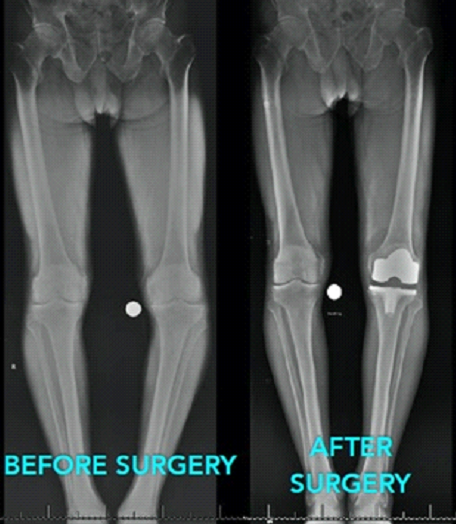

Similarly In TKR knee joint is replaced on both sides with metallic implant.in TKR both sides can be done together or done in staged manner one side at a time followed by other side